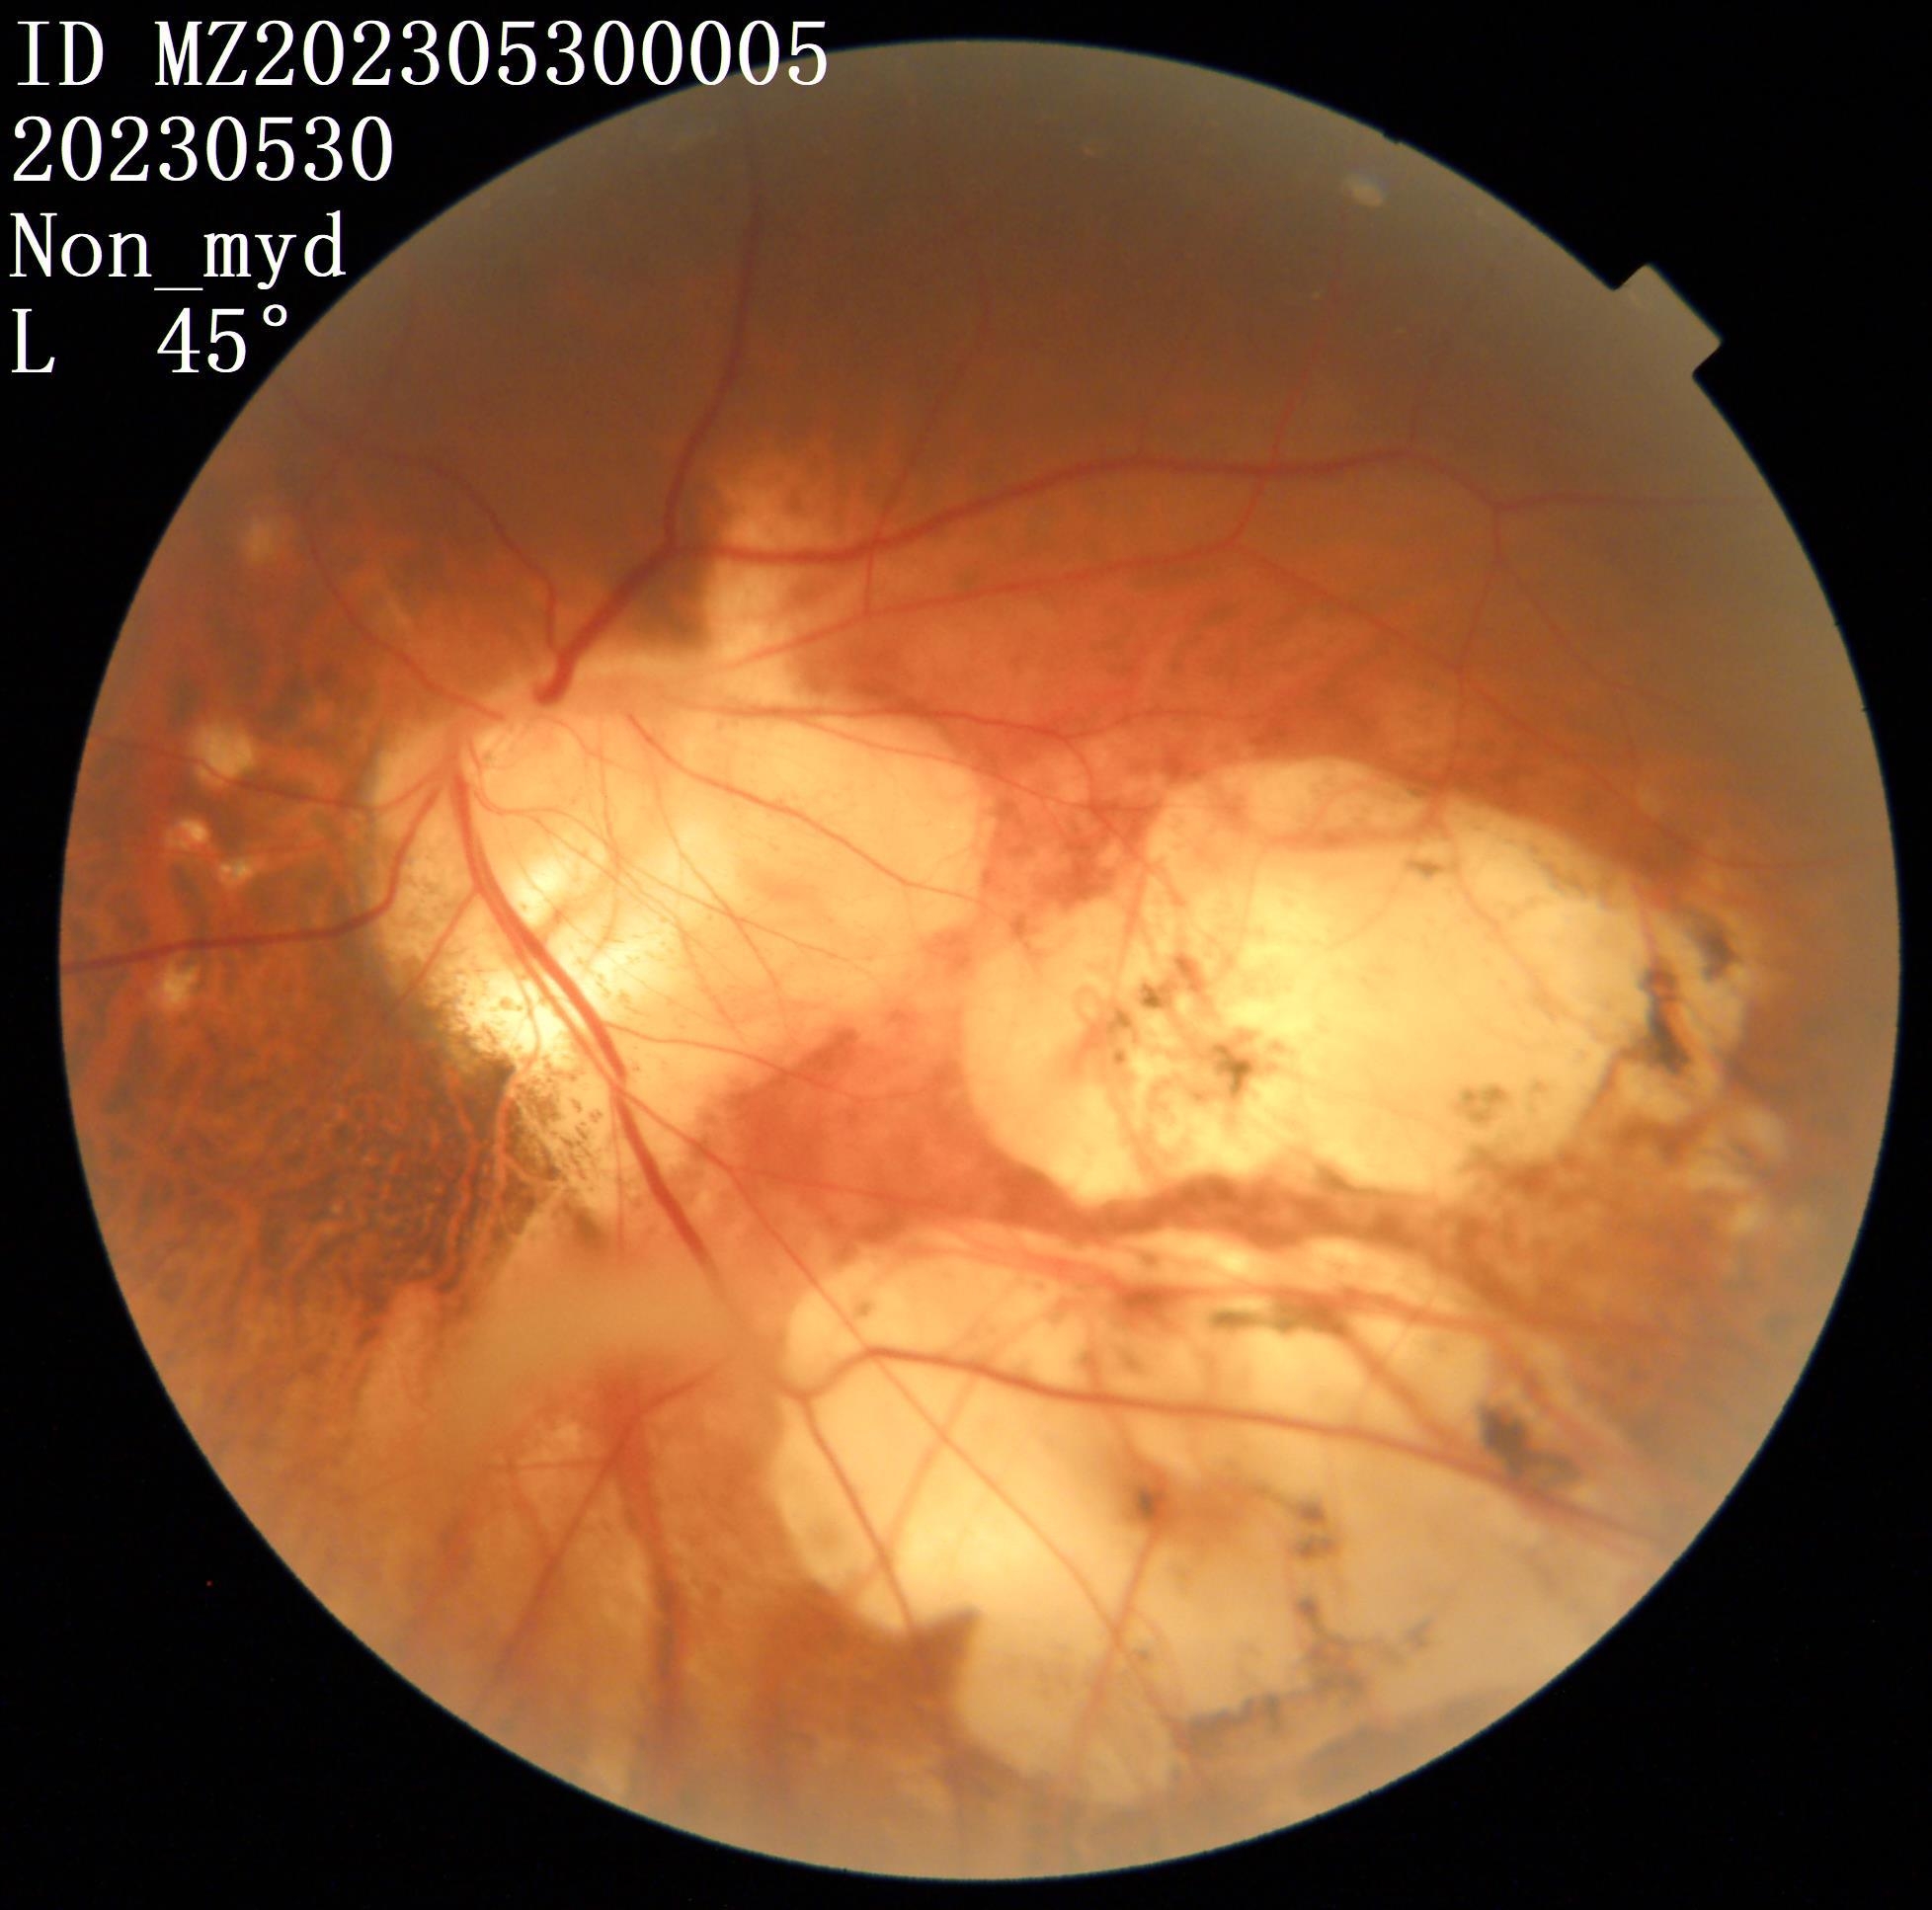

我检查以后发现他双眼的裸眼视力都非常差,右眼只有50公分数指,左眼只有0.02,矫正视力右眼戴2000度眼镜勉勉强强可以看0.05,左眼戴1900度眼镜也只能勉勉强强看到0.15,双眼晶状体轻度浑浊,玻璃体浑浊。最令我吃惊的是老人家双眼黄斑区视网膜不仅萎缩得像一张薄纸,而且还有劈裂性脱离及视网膜下陈旧性疤痕形成。

左眼手术以前底(萎缩、劈裂性脱离及视网膜下陈旧性疤痕)

左眼手术以前照片